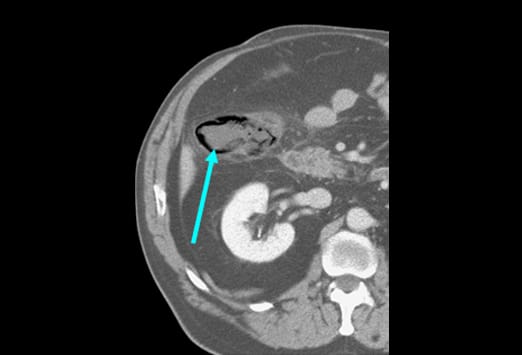

In dieser Abbildung reicht die Appendix hinauf bis zur Leber. Die Appendix liegt in bis zu 65% der Fälle retrocoecal. Bei Patienten mit einer retrocoecal gelegenen Appendizitis ist der Schmerz oft schlecht zu lokalisieren. Diese Patienten geben diffuse Beschwerden beim Husten oder Schmerzen in der in der Flanke an, seltener haben sie Schmerzen im rechten Unterbauch. Bei bis zu 15% der Patienten kann die Appendix nicht dargestellt werden. Dies gilt insbesondere bei Patienten mit einem geringen Anteil von intraabdominellem Fett. Von einigen Ärzten wird behauptet, dass eine nicht darstellbare Appendix eine Appendizitis ausschließt, [3] allerdings kann eine nicht erfolge Lokalisationsdiagnostik in diesen Fällen zu einer falsch-negativen Diagnose führen. In diesen Fällen ist es sinnvoll, eine engmaschige Verlaufskontrolle zu empfehlen.